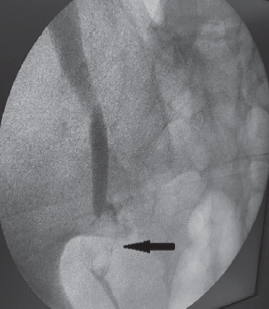

Пациент К., 68 лет, в мае 2017 г. поступил по срочным показаниям в кардиологическое отделение ПГКБ им. Е.Е. Волосевич с жалобами на нехватку воздуха, общую слабость. В анамнезе острый инфаркт миокарда, стентирование коронарных артерий в 2013 г. Получает консервативное лечение по поводу доброкачественной гиперплазии предстательной железы. При обследовании выявлены гиперкалиемия (6,4 ммоль/л), гиперкреатининемия (267 мкмоль/л), повышение мочевины крови до 18 ммоль/л. При УЗИ почек обнаружена двусторонняя выраженная пиелоэктазия. Пациент консультирован урологом — диагностирована доброкачественная гиперплазия предстательной железы, осложненная двусторонним гидроуретеронефрозом. Выполнена двусторонняя пункционная нефростомия. При контрастировании ультравистом выявлено выраженное расширение чашечно-лоханочных систем и верхних отделов мочеточников с двух сторон. Заподозрены стриктуры обоих мочеточников. Пациент обследован в урологическом отделении ПГКБ в марте 2018 г. При цистоскопии патологии не выявлено. Произведена двусторонняя уретероскопия до уровня стриктур, выполнена биопсия из участков, подозрительных на опухоль. Гистологическое заключение не подтвердило наличия опухоли. При цитологическом исследовании мочи атипичные клетки не обнаружены. Пациент консультирован онкоурологом — данных за онкозаболевание на момент осмотра не получено. Оперативное лечение по поводу стриктур мочеточников было отложено до января 2019 г. из-за обострений хронического пиелонефрита. 17 января 2019 г. накануне операции произведена двусторонняя антеградная пиелоуретерография, которая показала наличие справа в нижней трети мочеточника мягкотканного образования размером 2 × 2 см, обтекаемого контрастом (симптом «змеиного жала») (рис. 5).

Рис. 5. Пациент К., 68 лет. Антеградная пиелоуретерография справа. Стрелкой отмечено расширение мочеточника в нижней трети, обтекаемого контрастом («симптом змеиного жала»)

Fig. 5. Patient K., age 68. Antegrade pyeloureterograpy right. The arrow indicates the expansion of the ureter in the lower third, streamlined in contrast (“snake sting symptom”)